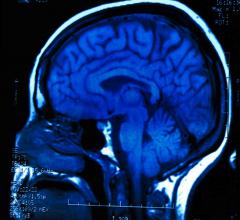

April 27, 2016 — Patterns of brain activity thought to show pain responses have been called into question after ...

April 26, 2016 — Repeated head impacts to high school football players cause measurable changes in their brains, even ...

April 21, 2016 — Using a sophisticated magnetic resonance imaging (MRI) technique, researchers have found abnormalities ...

April 13, 2016 — As chronic traumatic encephalopathy (CTE) stands in the national spotlight for high impact sports, the ...

April 11, 2016 — More than 40 percent of retired National Football League (NFL) players in a recent study had signs of ...

March 31, 2016 — New research suggests that looking at structures in the right side of the brain may help predict who ...